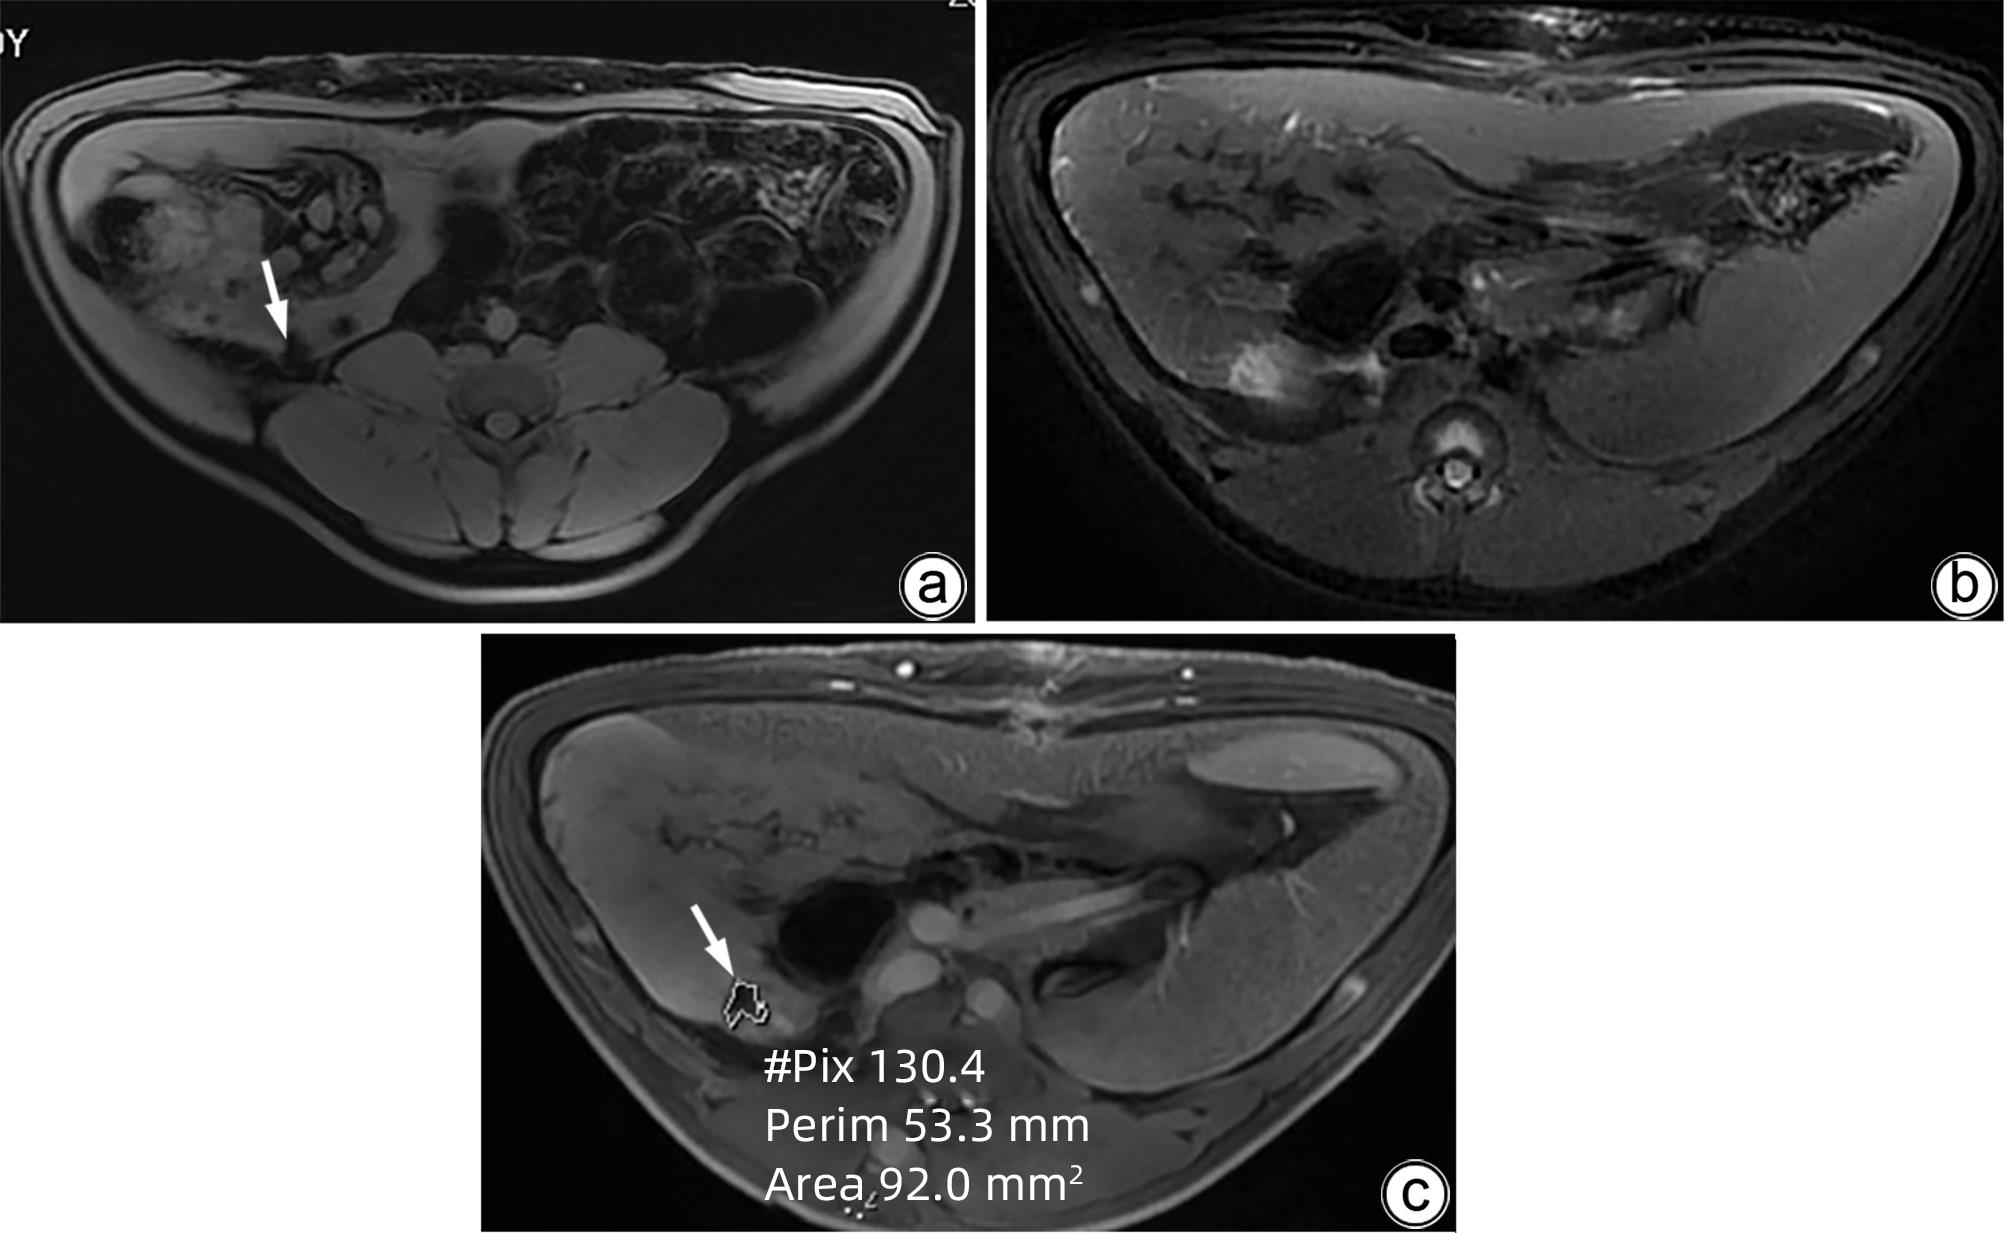

Standard for diagnosis and treatment of primary liver cancer (2024 edition)

2024, 40(5): 893-918. DOI: 10.12449/JCH240508